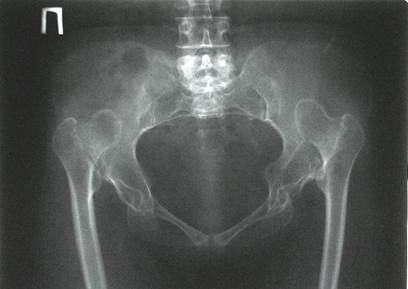

Дисплазия — это врожденный дефект строения ТБС, для которого характерна неправильная ориентация суставных компонентов. Дисконгруэнтность головки бедренной кости и вертлужной впадины приводит к функциональной перегрузке определенных частей сустава. Постоянная механическая травматизация вызывает дегенеративные изменения в суставных хрящах, капсуле и субхондральных костных структурах. В результате у больного развивается ранний деформирующий остеоартроз.

Тяжелая степень дисплазии.

По разным литературным данным, врожденные дефекты строения ТБС приводят к развитию диспластического коксартроза в 40-87% случаев.